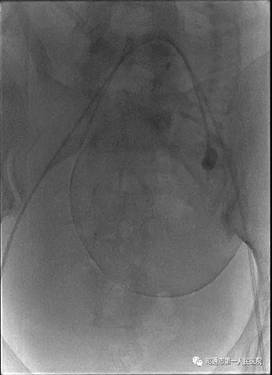

近日我院产科收治了一名由县级医院转入的孕妇。该孕妇年龄33岁,孕期多次B超提示:中央性前置胎盘伴植入可能。孕妇于2012年在其他医院行剖宫产术,2017年因瘢痕妊娠在云大医院行介入下手术。该孕妇入院后科室手术团队反复在科内B超下评估,结合她的病史及辅助资料考虑该患者胎盘植入的可能性很大,病情危急,决定术前邀请请普三科主任赵雄会诊。经会诊后拟术前行双侧髂内动脉球囊导管临时置入术。

术中见子宫下段血管丰富,怒张明显,胎盘广泛植入于子宫下段,伴穿透。如果按传统的胎盘打洞开窗取胎手术,孕妇可能瞬间大出血,危及生命。产科主任曹华及团队医师临时应变,经讨论决定借鉴省内外处理凶险性前置胎盘成功的经验,大胆探索子宫双切口术式,在接近宫底部取第一切口娩出胎儿后,由普三科手术团队行双侧髂内球囊临时阻断,子宫切口出血立即减少,剥离子宫切口周围胎盘组织,关闭第一切口。下推膀胱于子宫下段取第二切口,手剥胎盘,关闭第二切口。